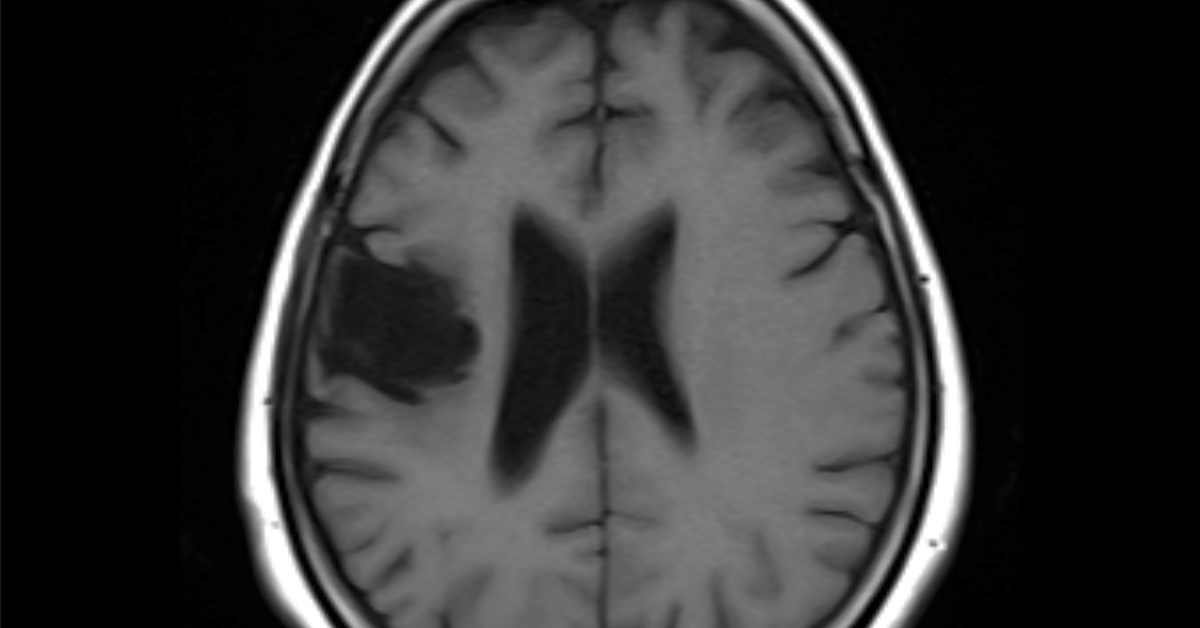

Public discussion often searches for one neat answer, but the disease rarely works that way. The National Institute on Aging says Alzheimer’s likely develops through several forces acting together over time. Age is the biggest known risk factor, and the aging brain can undergo inflammation, blood vessel damage, shrinking of key regions, and reduced energy production within cells. Against that background, the new study offers a more specific idea. It suggests that once amyloid-related stress is present, this protein pair may help turn that stress into cell injury. For readers, the takeaway is practical. The study is less about what starts Alzheimer’s and more about what may keep it moving in a destructive direction. The location of the protein pairing also matters. The study found more of this harmful interaction in the brains of 5xFAD mice than in healthy mice.

That point is easy to overlook, but it is crucial. A mouse can seem smarter on a task simply because it is more active or less anxious. The open field test found no meaningful effect of genotype or treatment on general movement. That strengthens the memory findings because it makes a simpler explanation less likely. Dr. Jing Yan, formerly part of Bading’s team and now with FundaMental Pharma, said that in treated Alzheimer’s mice, “disease progression was markedly slowed.” That quote came from the university material summarized by ScienceDaily, and it matches the overall pattern reported in the paper. The brain changes were just as striking as the behavioral ones. Untreated 5xFAD mice showed more damaged mitochondria in the hippocampus, the brain region deeply involved in memory.

Mitochondria are often called the cell’s powerhouses, and that analogy is useful here. They help cells produce the energy needed to function. When they are damaged, brain cells become less able to cope with stress. The study found that FP802 helped preserve mitochondrial structure and reduced the shift toward swollen, abnormal forms. It also helped preserve dendrites and synapses, which are the branches and contact points nerve cells use to communicate. In practical terms, the drug seemed to protect both the wiring and the energy supply of vulnerable brain cells. That combination of stronger memory and healthier brain tissue gives the study its force. Many experiments change a molecule without changing its behavior. Here, the researchers saw both. That does not settle the case for humans, yet it gives the Alzheimer’s Death Switch idea a stronger foundation than a laboratory finding.